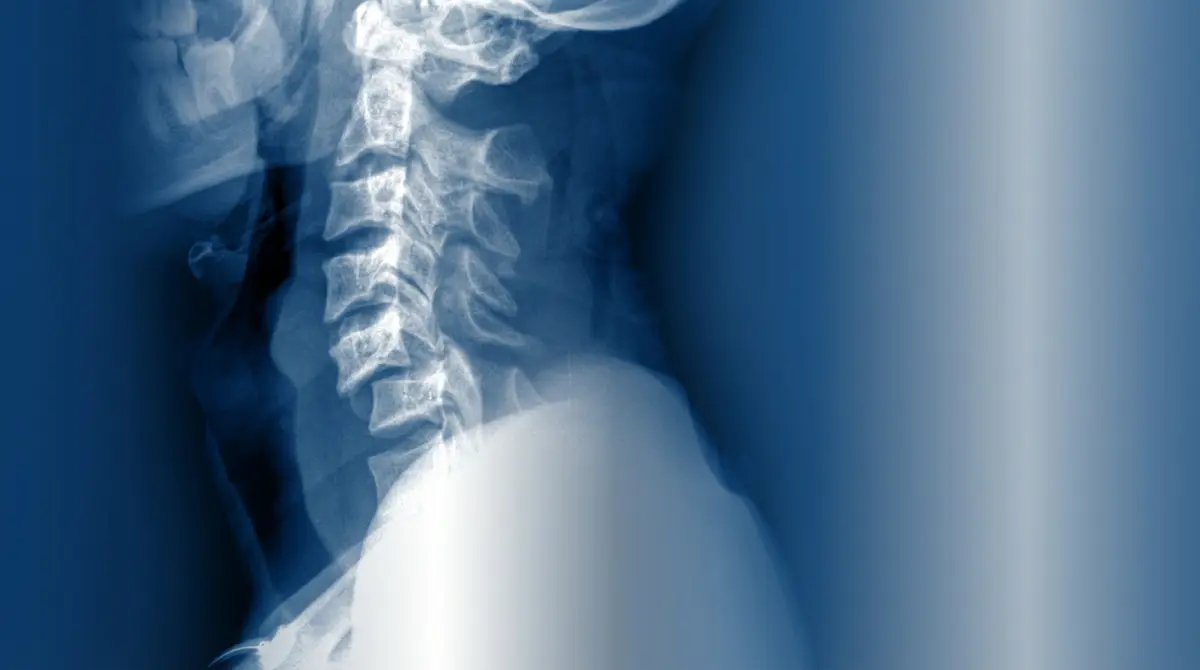

💥 Luxação Cervical Traumática com Compressão Medular

Deslocamento completo de uma ou mais vértebras cervicais em relação às outras, geralmente por trauma de alta energia (acidente de carro, mergulho raso, queda de altura). O deslocamento comprime, estica ou transectiona a medula espinhal, causando lesão neurológica severa e imediata.